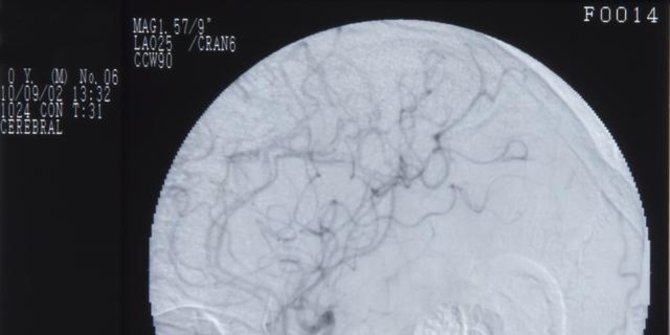

Terapi cuci otak ini pada dasarnya adalah metode diagnostik Digital Substraction Angiography (DSA), yang dalam bidang neurologi (ilmu saraf) dikenal dengan istilah cerebral angiography (CA).

Mengutip Healthline, cerebral angiography adalah tes diagnosis yang dilakukan menggunakan X-ray. Metode ini akan memproduksi gambar (cerebral angiogram) yang akan membantu dokter menemukan penyumbatan atau ketidaknormalan lain pada pembuluh darah di kepala dan leher.